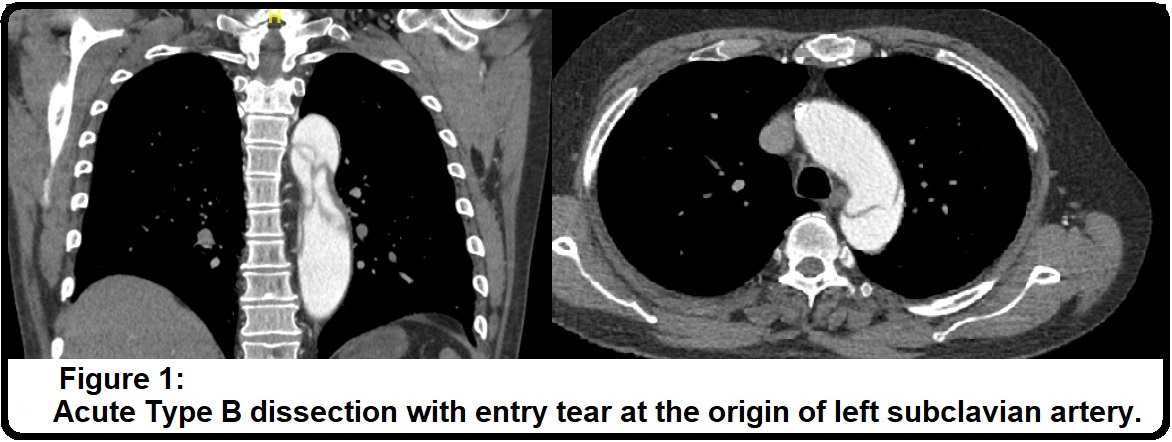

The patient in this video was a 69-year-old man who presented to the emergency department with sudden onset of chest and back pain. He was a smoker, otherwise there was no significant comorbidity, however, on admission he was markedly hypertensive. CT aorta revealed an acute type B dissection with an entry tear at the origin of the left subclavian artery; left kidney was malperfused and true lumen was significantly compressed by the false lumen (Figure 1). He developed acidosis that was a sign of organs ischaemia. He underwent emergency procedures that included left carotid-subclavian arteries bypass graft with 6 mm Dacron graft and percutaneous thoracic endovascular arterial repair in Ishimaru's zone 2, 3, 4 (TEVAR-Stent; Conformable GORE® Thoracic Endoprosthesis) (Figure 2). He was discharged on the sixth postoperative day in good condition. Subsequent CT scan showed the diameter of the ascending aorta 53 mm, while coronary angiogram revealed LAD stenosis (tight stenosis just before septal branch, moderate disease in mid segment), LCX stenosis (severe disease in LCX mid vessel), and RCA stenosis (Occluded at middle with distal collateral) (Figure 3). Transthoracic echocardiogram showed trivial aortic regurgitation, 39 mm sinus diameter and normal LV & RV systolic function.